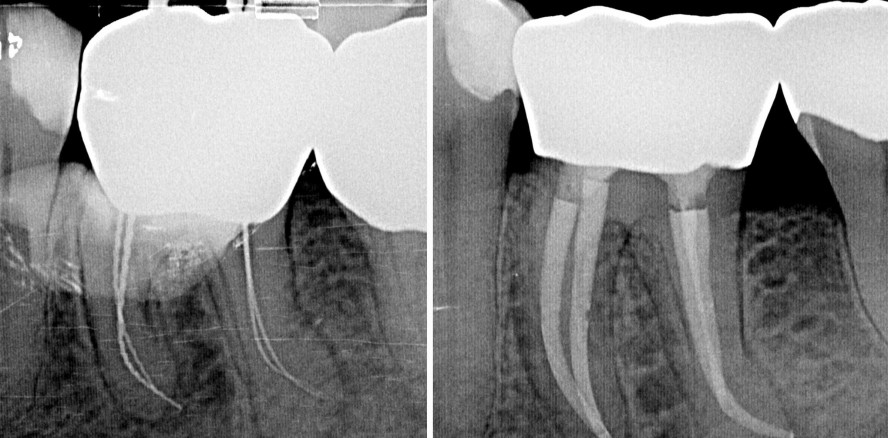

Unterer Molar mit Obliteration des mesiolingualen Kanals

Der folgende Fall eines unteren Molaren mit Obliteration des mesiolingualen Kanals zeigt, dass durch adäquate technische Ausstattung und Grundwissen über die Anatomie des Pulpakammerbodens Komplikationen vermieden werden können und die Behandlung vorhersagbar durchgeführt werden kann.

Eine 54-jährige Patientin wurde zur Weiterbehandlung des Zahns 36 an uns überwiesen. Nach Diagnosestellung einer akuten Exazerbation einer chronischen apikalen Parodontitis durch den Hauszahnarzt erfolgte dort die initiale Schmerztherapie in Form der Trepanation der Pulpenkammer, Darstellung der bukkalen Kanäle, medikamentöser Einlage und provisorischem Verschluss. Der überweisende Kollege konnte den mesiolingualen Kanal nicht darstellen und überwies die Patientin mit Verdacht auf Obliteration des Kanalsystems. Am Tag der Vorstellung in unserer Praxis bestand eine laut Patientin leicht gemilderte Symptomatik.

Das präoperativ angefertigte Röntgenbild zeigt den Zahn 36 nach Trepanation und provisorischem Verschluss durch den zuweisenden Kollegen. Die mesiale und distale Wurzel weisen periapikale Osteolysen im Sinne einer chronischen apikalen Parodontitis auf (Abb. 1).

Die primäre endodontische Behandlung des Zahns 36 erfolgte in zwei Sitzungen. Nach Anlegen des Kofferdams wurde die provisorische Füllung entfernt und die Zugangskavität mit 6 % Natriumhypochlorid gereinigt. Im Anschluss erfolgte die intrakoronale Diagnostik mit dem Dentalmikroskop. Es zeigte sich ein vom Vorbehandler erweitertes mesiobukkales und distobukkales Kanalorifizium (Abb. 2). Der distolinguale Kanaleingang stellte sich als schlitzförmige linguale Verlängerung des distobukkalen Kanals dar (Abb. 3). Nach initialer Sondierung mittels Micro-Opener wurde der Kanal mit einer EdgeFile® X7 (Henry Schein Dental) der Größe 17.06 koronal erweitert. Mesiolingual konnte Tertiärdentin im Bereich des obliterierten Kanalorifiziums dargestellt werden (Abb. 4). Der obliterierte Kanaleingang wurde mit langschaftigen Rosenbohrern sukzessive in absteigender Größe präpariert (Abb. 5), bis eine initiale mechanische Erweiterung mit einer EdgeFile® X7 der Größe 17.04 möglich war. Die Erstellung des Gleitpfads konnte in allen Kanälen rein mechanisch durchgeführt werden. Hierbei kamen EdgeFile® X7 der Größen 17.04 und 17.06 zum Einsatz. Die Feilen wurden im Wechsel verwendet. Nach koronaler Erweiterung der 17.06 erfolgte der Wechsel zur Feile der Größe 17.04, die in kurzen pickenden Arbeitsbewegungen bis zum Erreichen der vorläufigen röntgenologisch bestimmten Arbeitslänge verwendet wurde. Bei Widerstand wurde die Feile 17.06 passiv auf die bisher erreichte Länge gebracht, um so danach das weitere Vordringen der 17.04 zu ermöglichen. Nach elektrometrischer Bestimmung der Arbeitslänge mit Handfeilen und Bestätigung per Instrumentenkontrastaufnahme (Abb. 2) erfolgte die weitere Präparation mit EdgeFile® X7 der Größen 25.06 und 30.06 unter kontinuierlicher Spülung mit 6 % NaOCl (Abb. 6 und 7). Im Anschluss wurde eine medikamentöse Einlage mit Kalziumhydroxid auf volle Arbeitslänge eingebracht und der Zahn provisorisch in Adhäsivtechnik verschlossen.

Die Weiterbehandlung fand nach zwei Wochen bei Beschwerdefreiheit statt. Nach erneuter elektrometrischer Kontrolle der Arbeitslänge und schallaktivierter Abschlussspülung mit 17 % EDTA und 6 % NaOCl für je 60 Sekunden je Kanal wurden die Kanäle in warm-vertikaler Fülltechnik mit Epoxidharz-Sealer gefüllt (Abb. 8 und 9). Der direkte adhäsive Verschluss des Zugangs erfolgte mit einem Bulk-Fill-Flow-Komposit (Abb. 10).